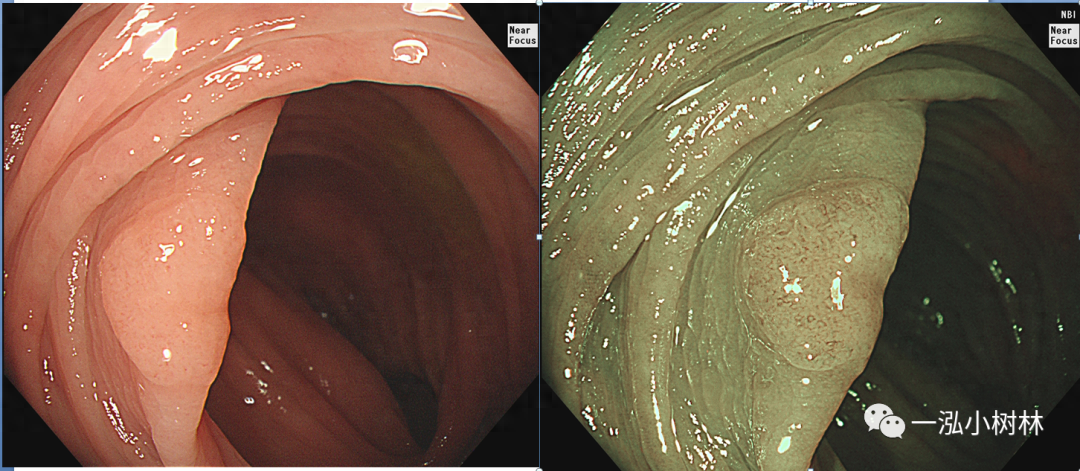

图1 结肠管状腺瘤(JNET2A型)